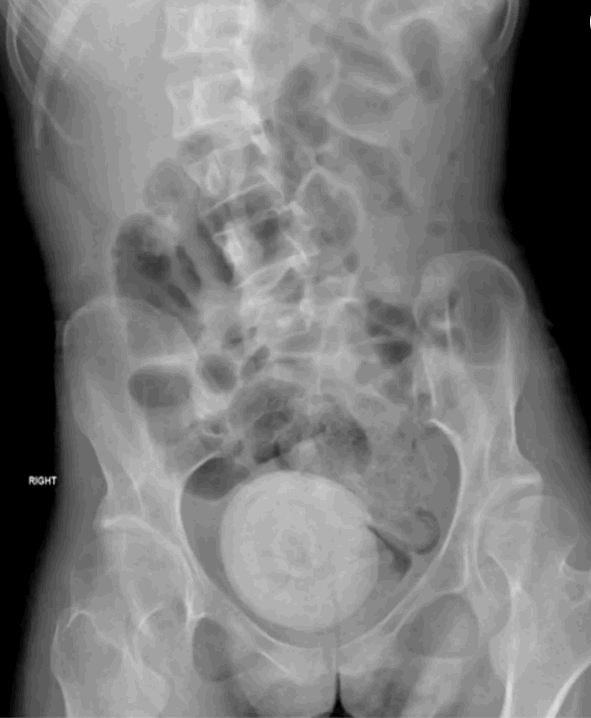

عثر أطباء في لبنان على حجر مهبلي نادر للغاية – بحجم برتقالة – موجود في حوض امرأة.

دراسة حالة حديثة نشرت في مجلة

Urology Case Reports

تناولت بالتفصيل الاكتشاف الاستثنائي - في هذه الحالة، لدى امرأة طريحة الفراش تبلغ من العمر 27 عامًا مصابة بالشلل الدماغي.

وكشف التصوير المقطعي للحوض والبطن عن السبب.

وتتشكل حصوات المهبل "عن طريق ترسب الأملاح غير العضوية عن طريق البول الراكد داخل المهبل"، وفقًا لورقة بحثية نُشرت عام 2019 في مجلة الطب. وقال الباحثون إنه بسبب ندرة هذه الحالة، فقد تم تشخيصها بشكل خاطئ في كثير من الأحيان في الماضي.

وكان التكوين كبيرًا جدًا لدرجة أنه كان يضغط على مثانة المرأة، مما أدى إلى المزيد من تسرب البول.

وقام أطباء من الجامعة اللبنانية في بيروت بفك التشكيل باستخدام العلاج بالليزر عبر الموجات فوق الصوتية من جهاز تم وضعه على بطن المرأة.

ثم استخدم الأطباء الملقط لإزالة الشظايا في إجراء مدته ثلاث ساعات.